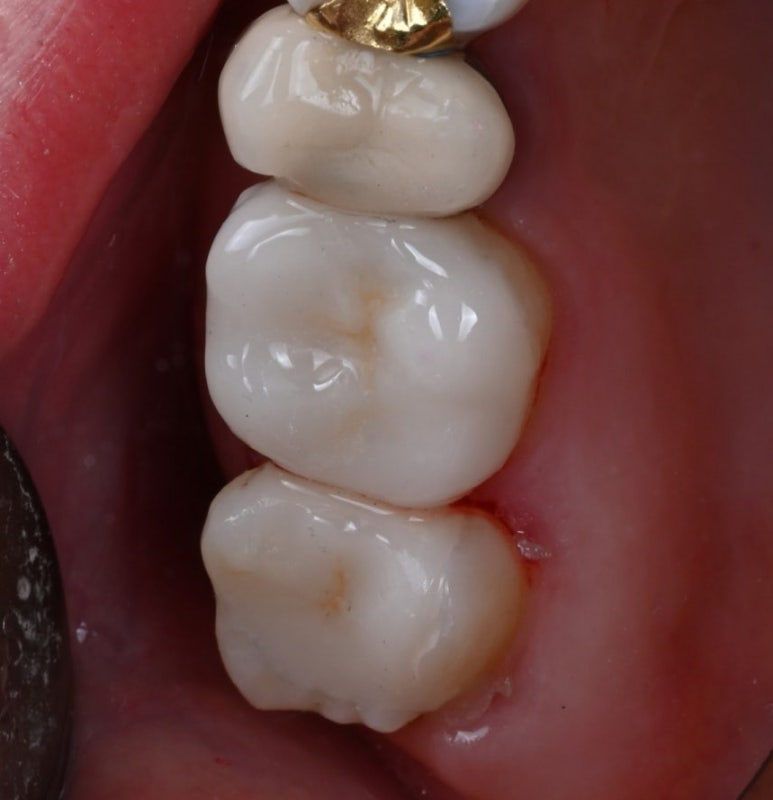

25.11.19 접착 후

25.11.19 교합조정까지 마친 후